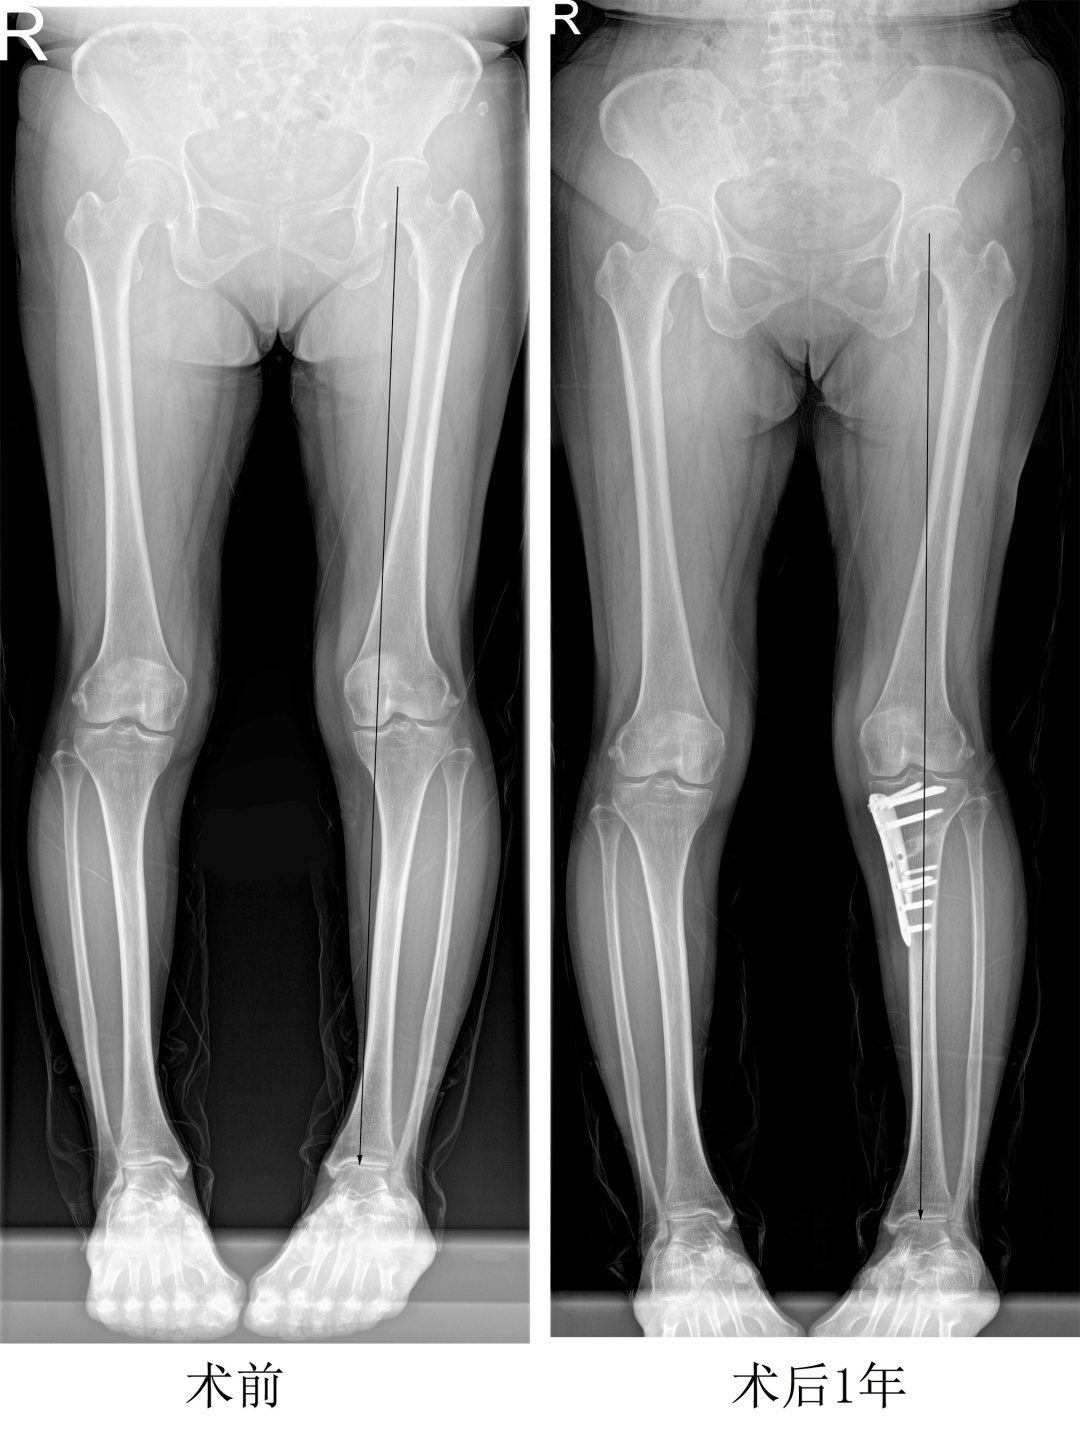

近日,67岁的徐阿姨来到同济大学附属同济医院运动医学科、骨关节外科中心复诊,她的左膝关节已无明显疼痛,膝关节活动已恢复正常。回想起去年这个时候,徐阿姨正饱受左膝关节疼痛不适的折磨。当时经家人介绍,她找到了同济大学附属同济医院运动医学科、骨关节外科中心主任程飚。程飚通过病史询问、查体及相关检查认为徐阿姨左膝关节痛、左膝关节退行性变是由于左下肢力线不良引起,建议行胫骨高位截骨术矫正下肢力线,将下肢力线从发生炎症和磨损的内侧间室转移到相对正常的膝关节外侧间室,减低内侧间室的压力,有效地阻止软骨的磨损,缓解膝关节疼痛症状。

在完善术前检查及相关术前准备后,程飚及其团队于去年11月为徐阿姨进行了关节镜下清理联合胫骨高位截骨术,手术非常成功,徐阿姨的左下肢力线得以有效矫正,左膝关节的疼痛和不适得到明显改善。

胫骨高位截骨术是指通过在胫骨近端进行高位截骨,将下肢力线从膝关节内侧间室转移到正常的膝关节外侧间室,从而达到缓解关节疼痛、减轻关节炎症状并延长膝关节寿命的目的。